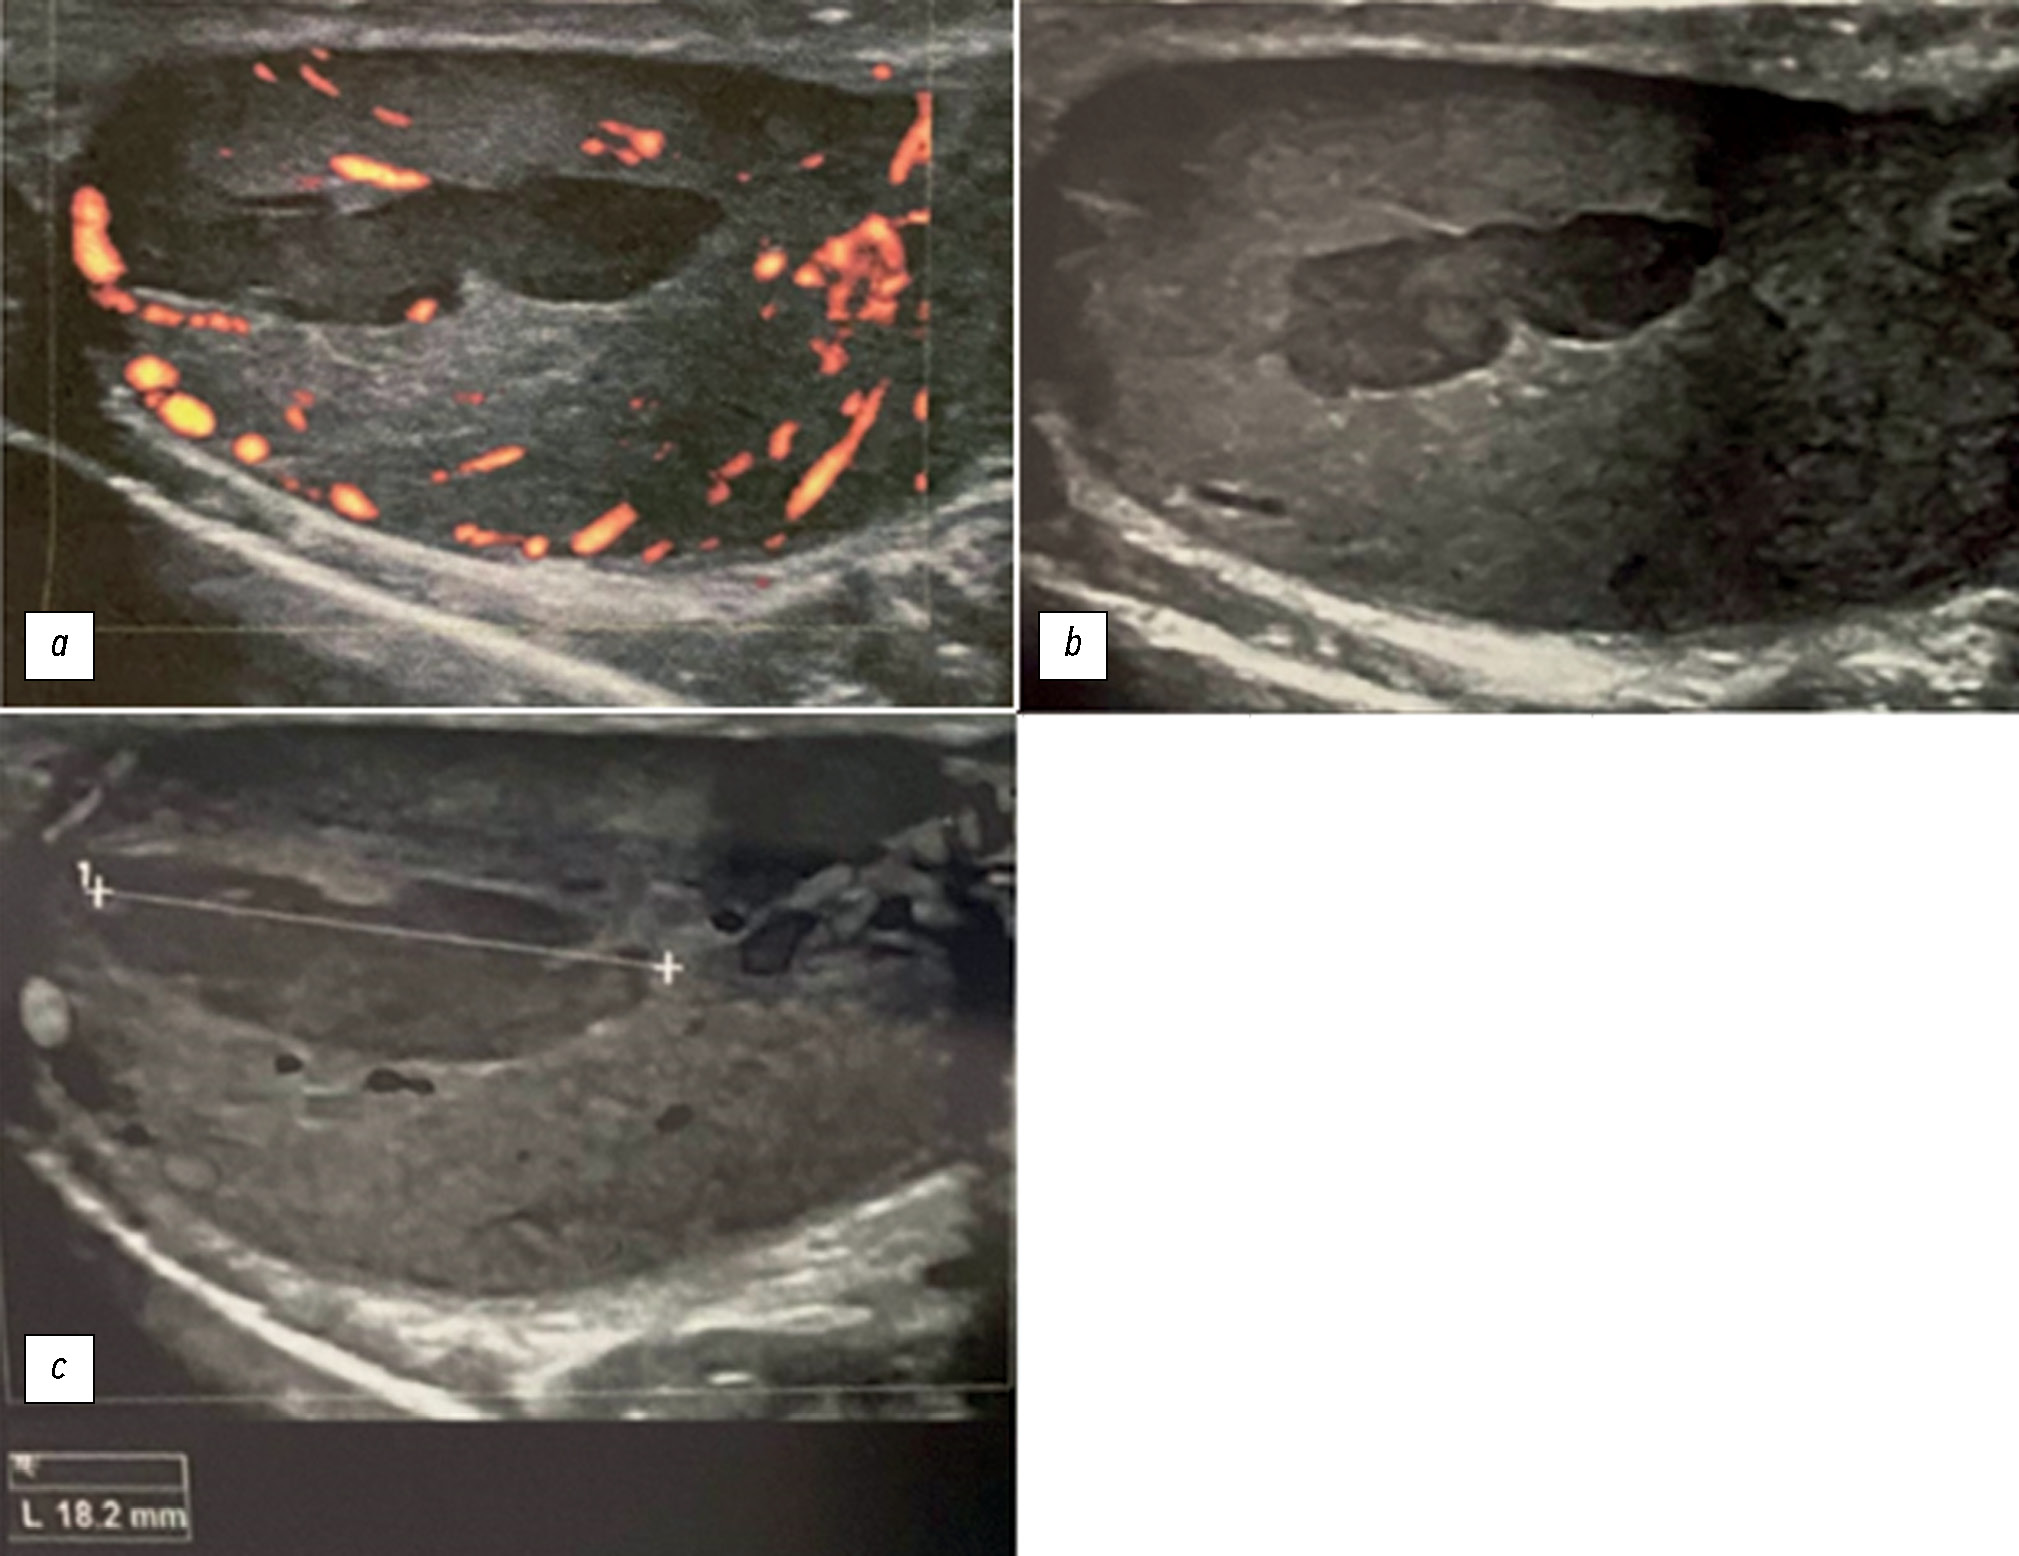

年轻患者左侧阴囊疼痛的睾丸缺血诊断:附睾炎的潜在致命并发症

在极少数情况下,急性附睾炎会伴有睾丸缺血和梗塞。 通过临床症状和影像学检查结果很难区分附睾炎和睾丸扭转。在本文中,我们努力扩大用于快速准确鉴别诊断的放射治疗诊断方法的数字图像库。本病例强调了全面放射检查的重要性,以及采用跨学科方法做出准确诊断的必要性。一名24岁的男子因两周前出现左侧睾丸剧烈疼痛而来到医院就诊。据患者称,已经有一段时间出现射精疼痛、性交疼痛、阴囊发红/肿胀、生殖器发炎、恶寒、腹股沟淋巴结肿大、排尿困难和阴囊疼痛。在泌尿科医生的建议下,接受了超声检查和核磁共振成像检查。 影像学检查显示左侧睾丸缺血。根据病史,怀疑患有慢性睾丸附睾炎。由于缺血范围有限,患者无需进行左侧睾丸切除术。 接受了药物治疗。此外,患者还被诊断为左侧精索静脉曲张。对不同磁共振成像序列获得的图像进行了仔细研究。本文描述了一例罕见的睾丸附睾炎病例,这是附睾炎的一种潜在危险并发症。为避免严重后果,当阴囊突然剧烈疼痛时,应考虑到这种并发症的可能性。此案例的描述,能够优化患者的管理方法,并避免不必要的干预。